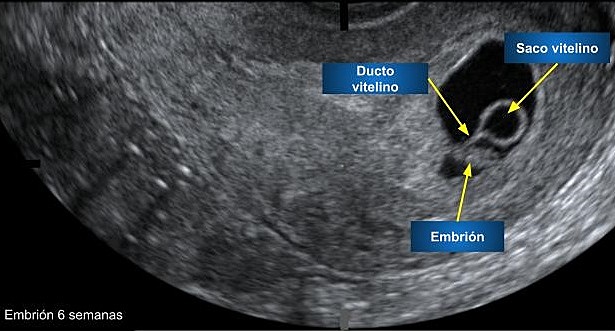

• 36-42 DÍAS SEXTA SEMANA

36-42 DÍAS SEXTA SEMANA

El tubo neural comienza a cerrarse.

Se forman los primordios del ojo y del oído, que se observan como unas manchas negras en ambos lados de la cabeza.

El cuello y tronco se enderezan.

El corazón late mas fuerte y rápido.